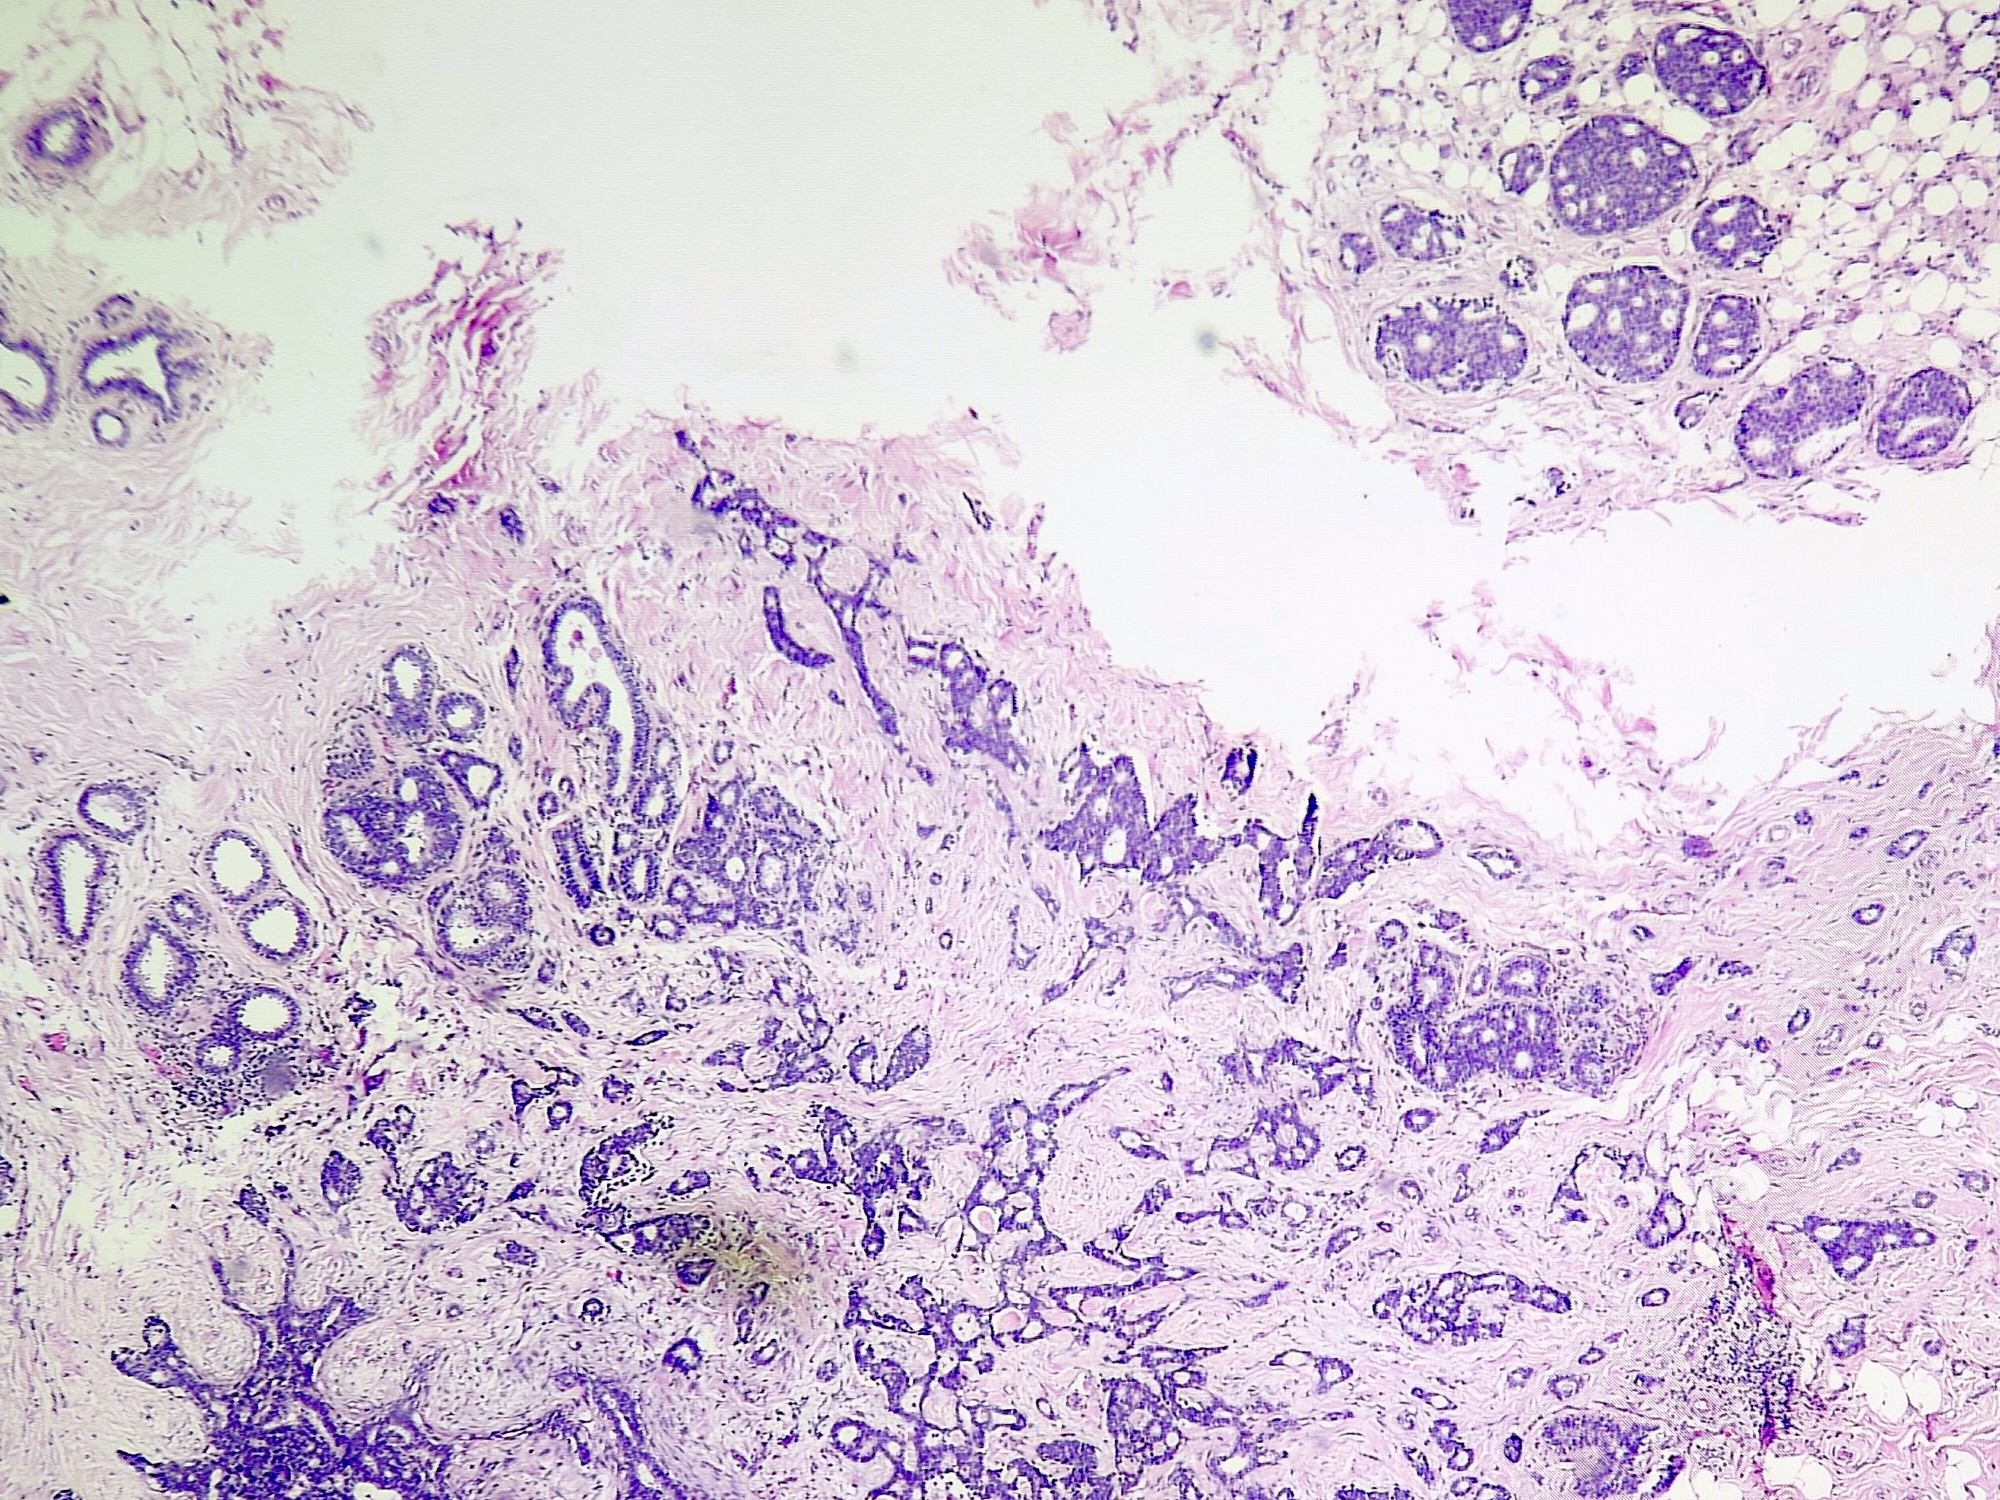

Microscopic (histologic) description

- Irregular cribriform growth pattern > 90% of cells

- Nuclear grade I pure ICC: > 90% cribriform pattern

- Mixed: 10 - 90% other morphological type, other than cribriform carcinoma

- Low grade: Nottingham grade 1 tumors

- Invasive islands or nests of malignant cells with round or angulated contours and well defined cribriform spaces formed by arches of epithelial cells; this gives a sieve-like appearance

- Tumor cells: small, mild / moderate pleomorphism, no nuclear atypia

- No / sparse mitotic activity

- Desmoplastic stroma

- Mucin positive secretion, microcalcifications in lumen

- Osteoclastic giant cells may be seen

- Myoepithelial cells absent

- Associated with cribriform ductal carcinoma in situ (DCIS)

Microscopic (histologic) images

Contributed by Sunitha Shankaralingappa, M.B.B.S, M.D., D.M.